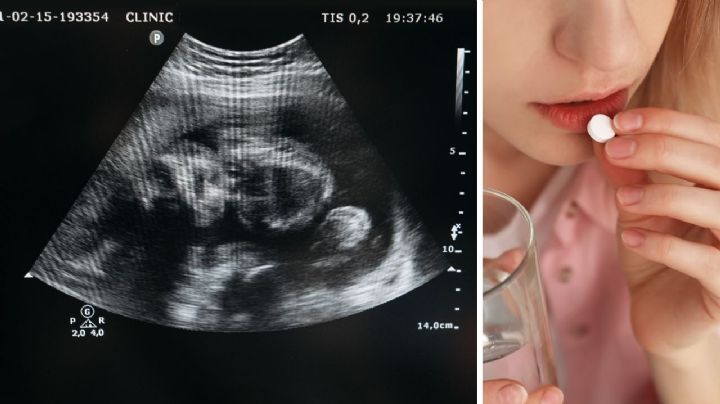

Corte declara inconstitucional castigar el aborto en Tamaulipas

22/4/2026 | La decisión deriva del amparo en revisión 426/2025, promovido por un grupo de ciudadanas que impugnaron disposiciones del Código Penal y de la Constitución local